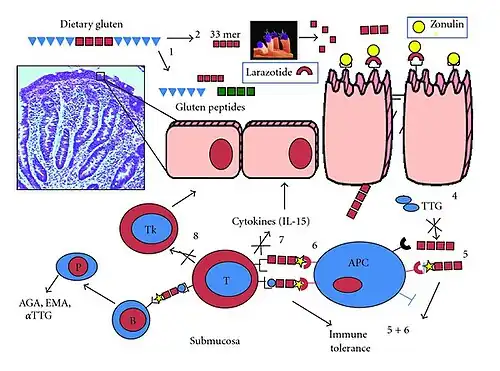

Tissue transglutaminase

Tissue transglutaminase modifies gluten peptides into a form that may stimulate the immune system more effectively.[43] These peptides are modified by tTG in two ways, deamidation or transamidation.[44]

Deamidation is the reaction by which a glutamate residue is formed by cleavage of the epsilon-amino group of a glutamine side chain.[45] Transamidation is the cross-linking of a glutamine residue from the gliadin peptide to a lysine residue of tTg in a reaction that is catalysed by the transglutaminase.[44] Crosslinking may occur either within or outside the active site of the enzyme. The latter case yields a permanently covalently linked complex between the gliadin and the tTg. This results in the formation of new epitopes believed to trigger the primary immune response by which the autoantibodies against tTg develop.[46]

Stored biopsies from people with suspected coeliac disease have revealed that autoantibody deposits in the subclinical coeliacs are detected prior to clinical disease.[43]

Villous atrophy and malabsorption

The inflammatory process, mediated by T cells, leads to disruption of the structure and function of the small bowel's mucosal lining and causes malabsorption as it impairs the body's ability to absorb nutrients from food.[32][31]

Alternative causes of this tissue damage have been proposed and involve the release of interleukin 15 and activation of the innate immune system by a shorter gluten peptide (p31–43/49).[43]

Many strategies have been proposed to develop new treatments for coeliac disease. Altering wheat to be safer for those with coeliac disease has been explored using methods such as genetic manipulation of wheat and using a chemical process (transamidation) that changes gluten proteins so they no longer trigger an immune reaction.[95][98] Medications and techniques such as chitosan and AGY gluten sequestering aim to prevent gluten from interacting with the immune system.[95] Glutenases are enzymes taken with food designed to help break down and neutralise gluten in the intestines. Glutenases being studied as of 2022 include latiglutenase–ALV003, Aspergillus niger prolyl endoprotease, Kuma030–TAK-062, and endoproptease-40.[98][7]

Larazotide acetate is a peptide that helps tighten the junctions between intestinal cells, reducing intestinal permeability. It helps decrease reactions to gluten by preventing gluten fragments from passing through the gut lining and triggering the immune system.[7] Treatments focused on immunomodulation aim to target the T cells that react to gluten and reduce intolerance to gluten.[98]